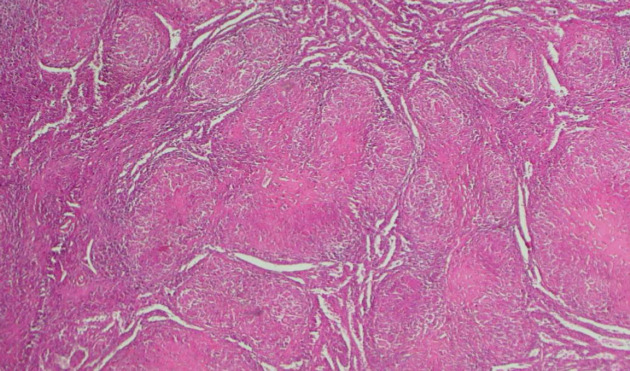

肉样瘤病是一种病因不明的多系统炎症性疾病。孤立的肺外病变非常罕见。我们报告了一例 29 岁女性患者的肝脾肉样肿大病。该患者无明显病史,因反复鼻衄就诊。临床检查发现肝脏结节性肿大,伴有门脉高压和脾脏肿大。血沉、碱性磷酸酶、血清血管紧张素转换酶和转氨酶均偏高。脾脏和肝脏活检组织学检查发现有肉芽肿性炎性浸润,但无癌症病变或扁桃体结石。主要的挑战仍然是与其他肉芽肿病的鉴别诊断。皮质类固醇疗法是一线治疗方法,脾脏切除术后,患者的临床和生物学状态均趋于稳定。

Sarcoidosis is a multisystem inflammatory disease of unknown etiology. The isolated extrapulmonary form is rare. We report the case of hepatosplenic sarcoidosis in a 29-year-old female patient.It is a patient with no notable medical history, who was seen in consultation for repeated epistaxis. Clinical examination noted nodular hepatomegaly associated with signs of portal hypertension and splenomegaly. Sedimentation rate, alkaline phosphatase, serum angiotensin converting enzyme, aminotransferases were high. Histological examination of the spleen and liver biopsy noted granulomatous inflammatory infiltration without cancerous lesion or tonsil stones.This picture is comparable with sarcoidosis, despite the absence of PET scans. The main challenge remains the differential diagnosis with other granulomatoses. Corticosteroid therapy is the first-line treatment, and after splenectomy the patient has achieved clinical and biological stability.